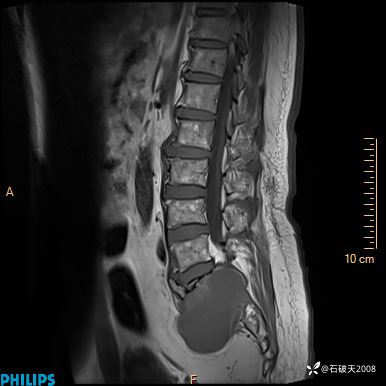

2023年3月份MRI影像

T1矢状位